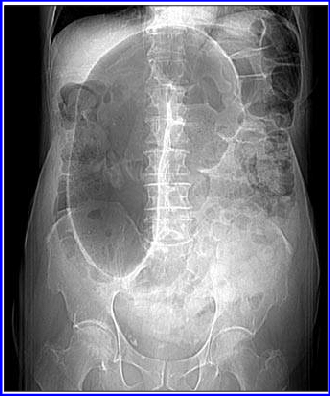

Chụp cắt lớp vi tính (CT Scan), chụp X-quang.

Click vào ảnh để xem 4 hình ảnh minh họa